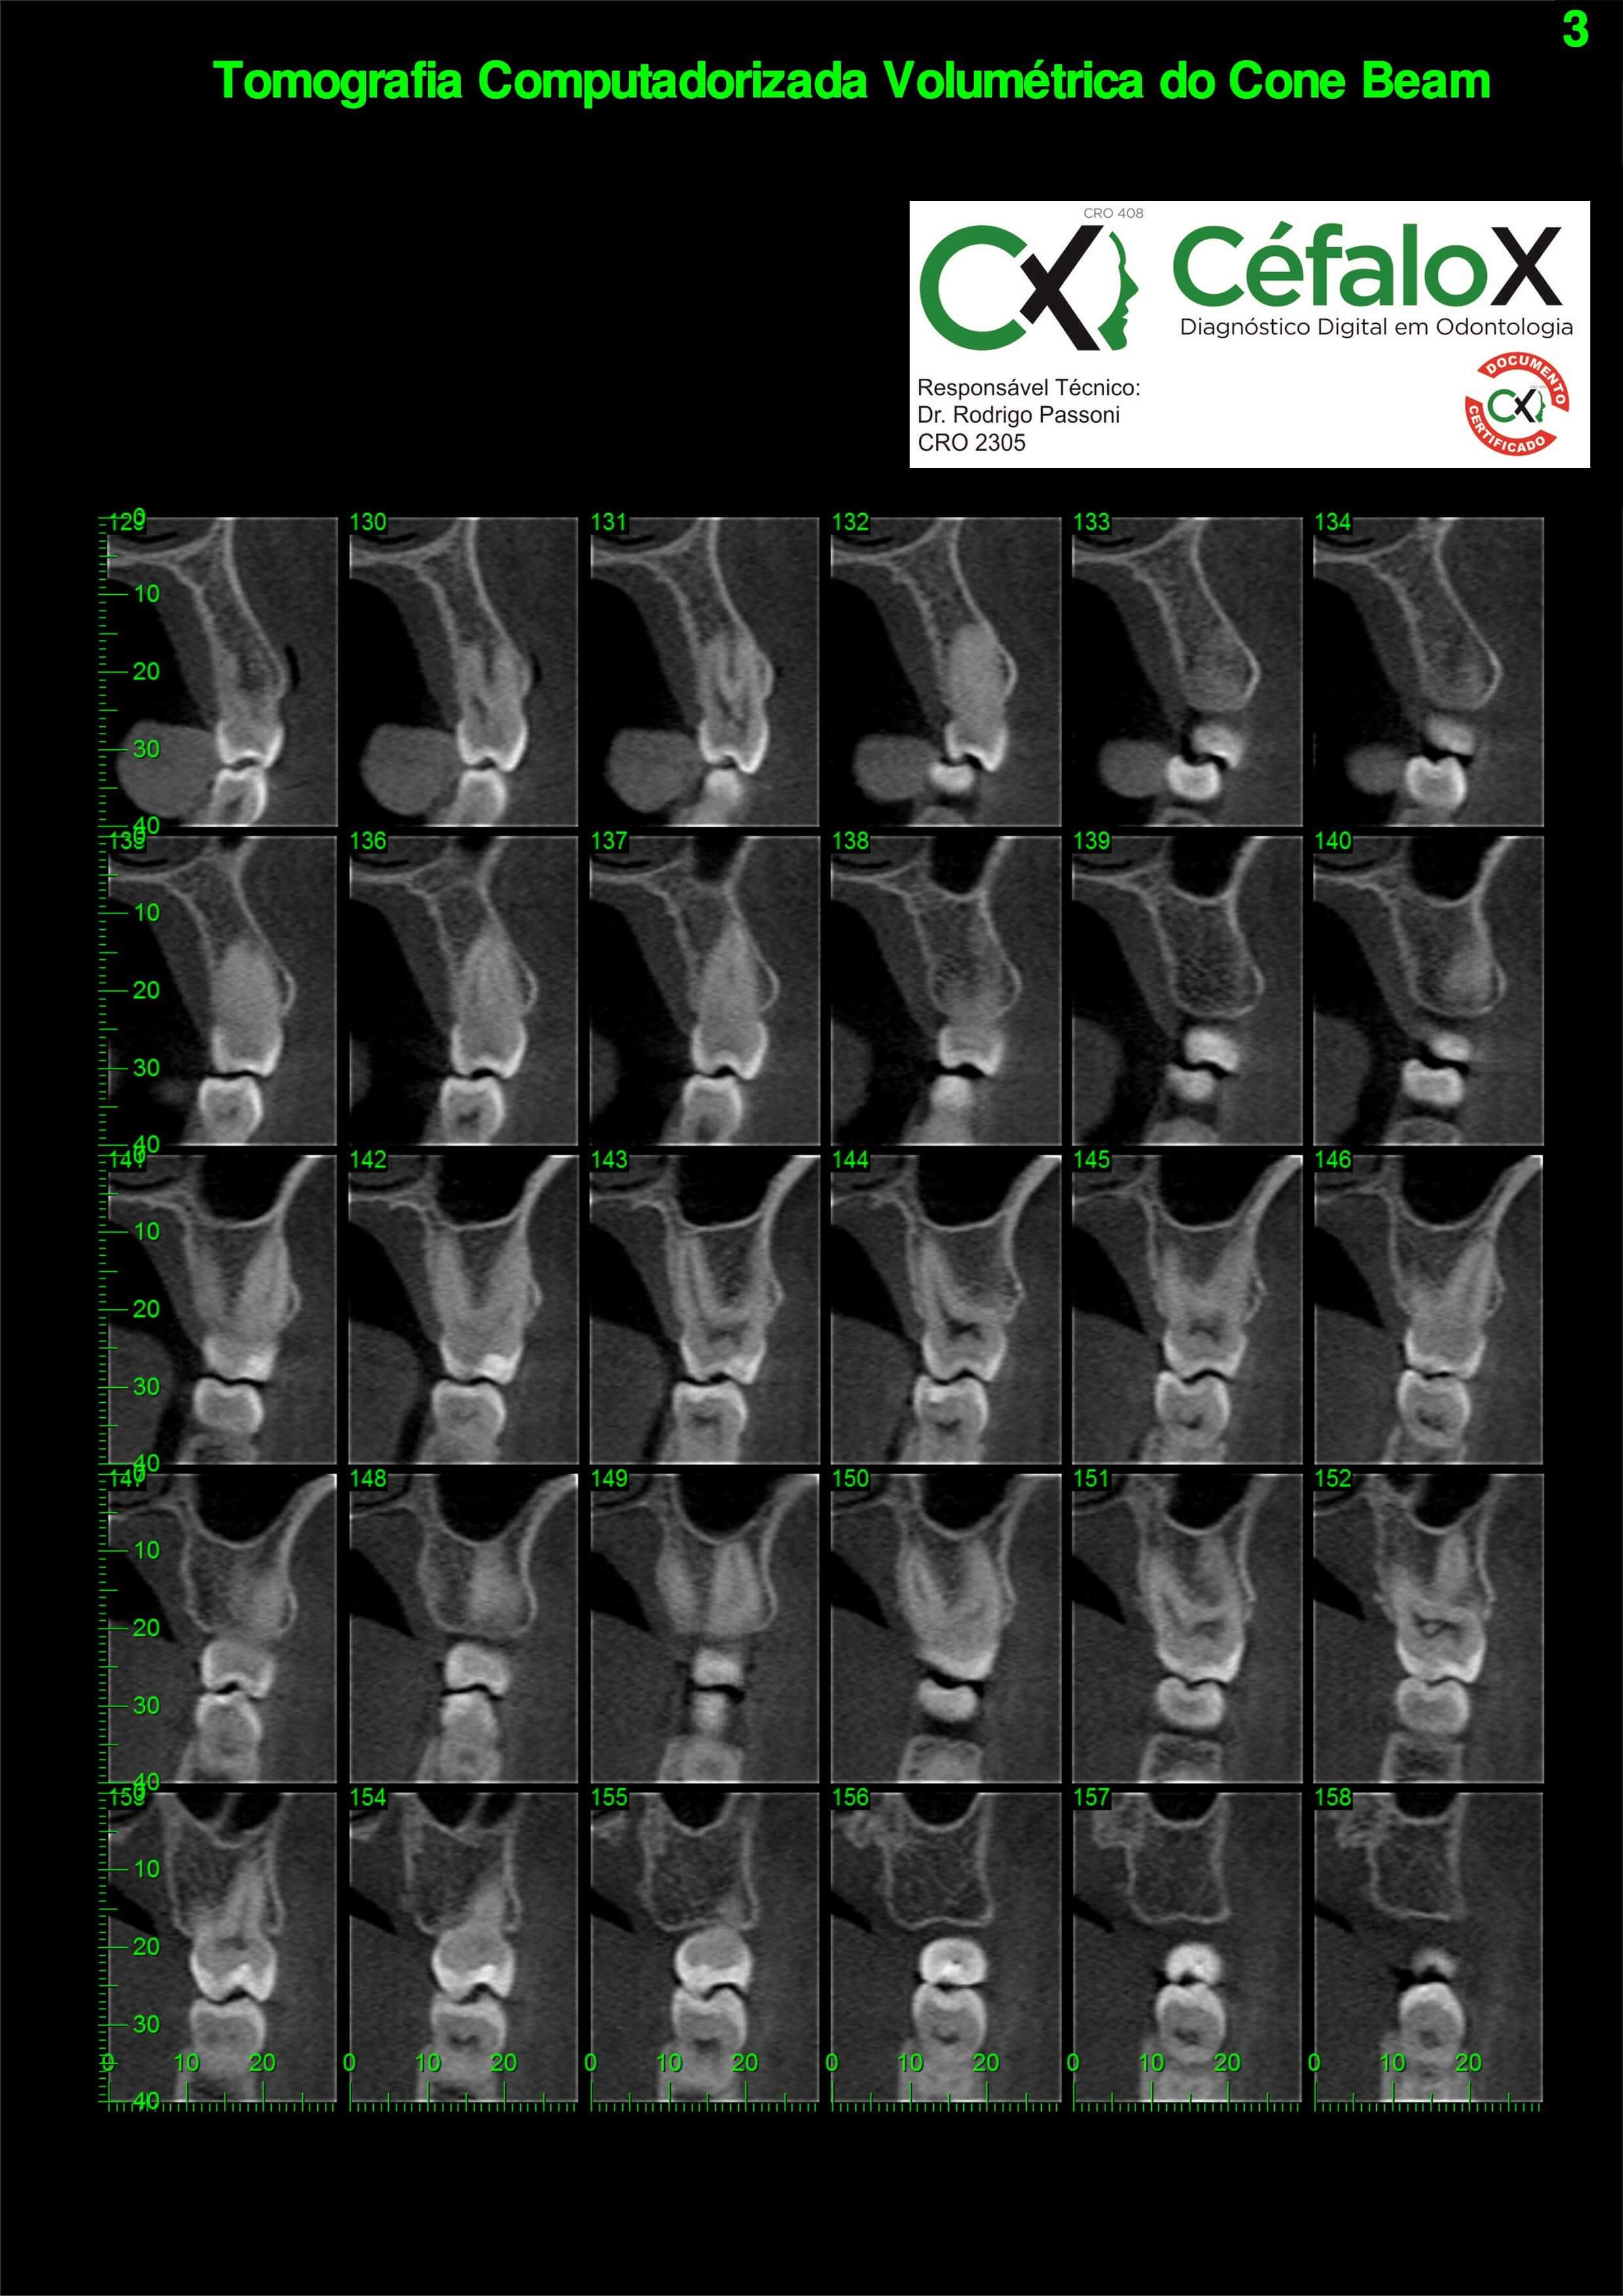

TC de face (do Hióide à Glabela), reconstruções 3D do tecido mole/ósseo/vias aéreas, radiografia panorâmica, telerradiografia lateral e frontal com traçado, cortes transversais e axial de maxila/mandíbula, ATM e arquivo DICOM – entregue em pasta e caixa de Pvc.